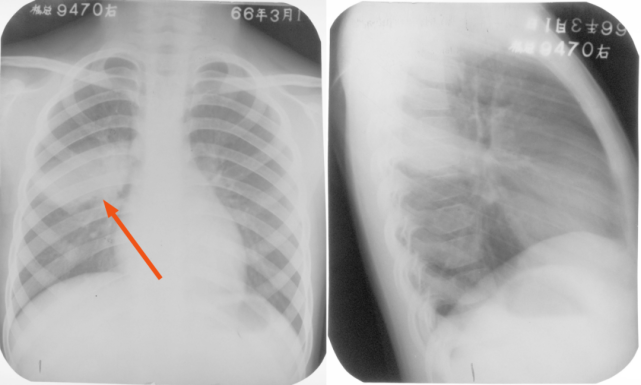

右上、下肺支原体肺炎

图片

胸部正位片示:右上、下肺野肺纹理增粗,可见斑片状阴影,密度较淡,局部呈扇形自肺门部发出(箭头所指)